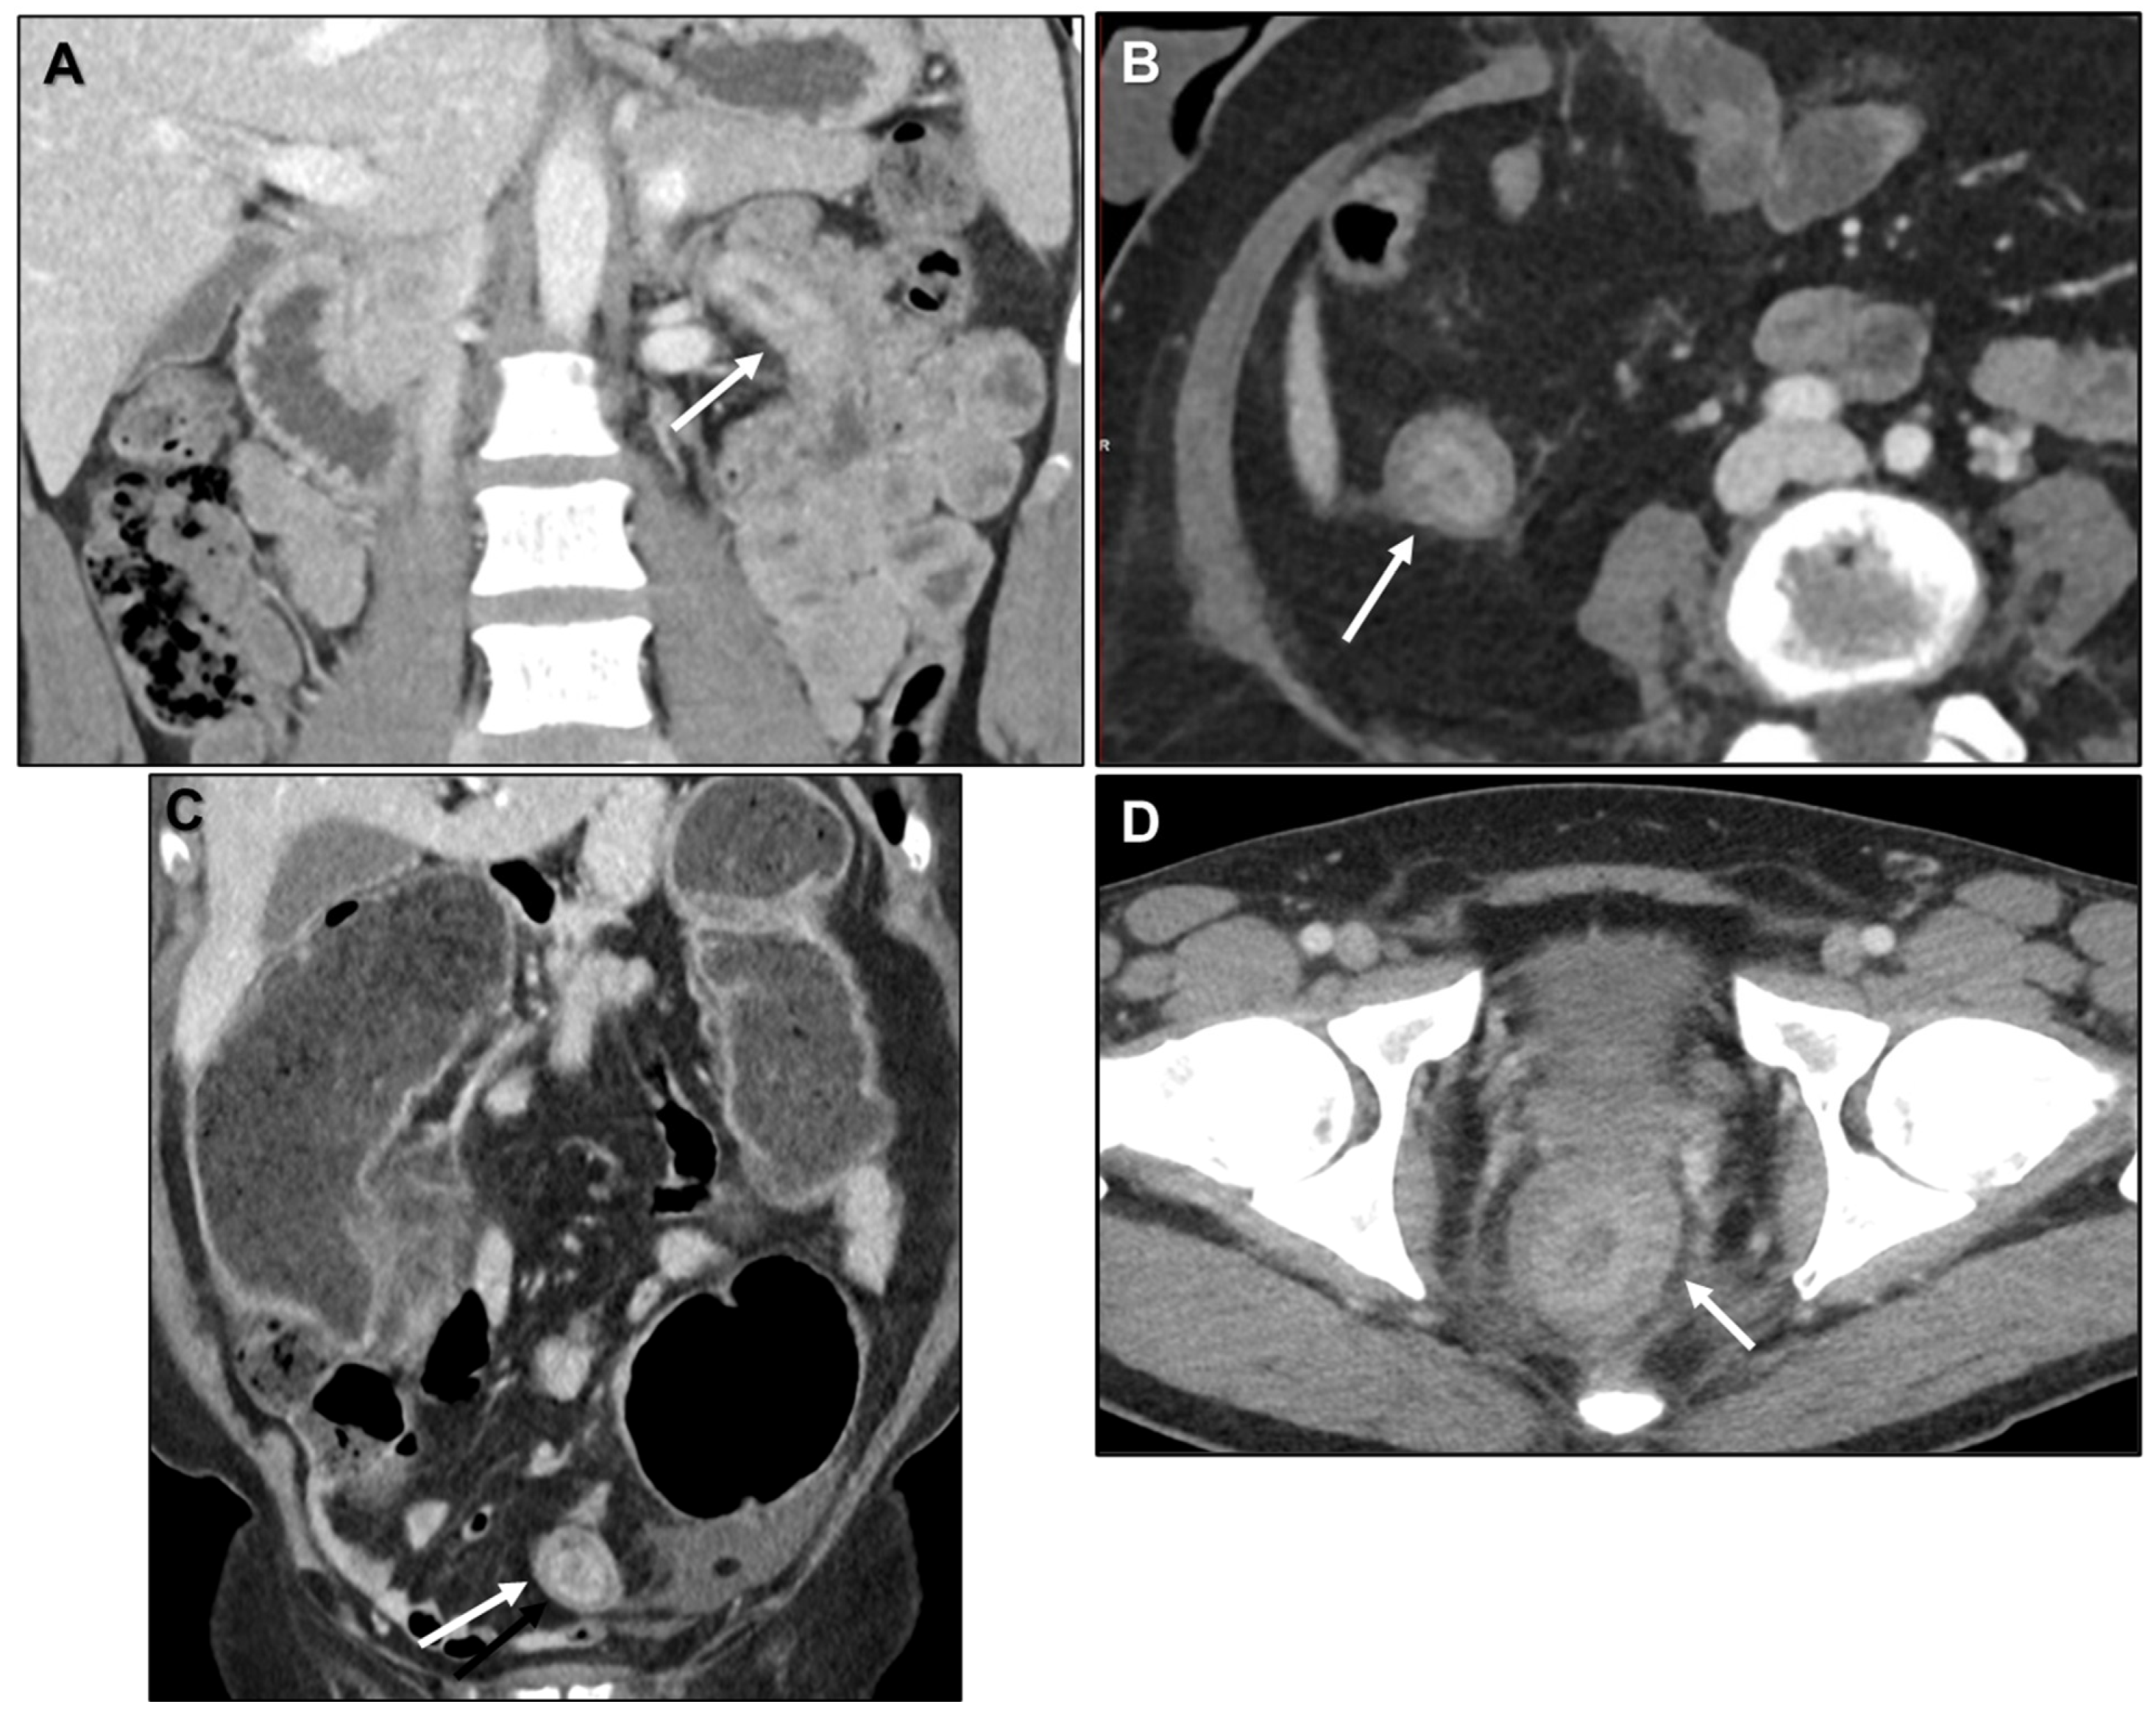

Peritoneal Carcinomatosis

Intestinal Obstruction

- Ha, H.K.; Jee, K.R.; Yu, E.; Yu, C.S.; Rha, S.E.; Lee, I.J.; Hee, J.Y.; Jin, C.K.; Kun, C.P.; Ho, Y. CT features of metastatic linitis plastica to the rectum in patients with peritoneal carcinomatosis. AJR Am. J. Roentgenol. 2000, 174, 463–466. [Google Scholar] [CrossRef]

- Burgain, C.; Germain, A.; Bastien, C.; Orry, X.; Choné, L.; Claudon, M.; Laurent, V. Computed tomography features of gastrointestinal linitis plastica: Spectrum of findings in early and delayed phase imaging. Abdom. Radiol. 2016, 41, 1370–1377. [Google Scholar] [CrossRef]